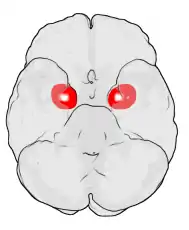

Frontal and side view of amygdala

Dorsal view of the amygdalae in an average human brain